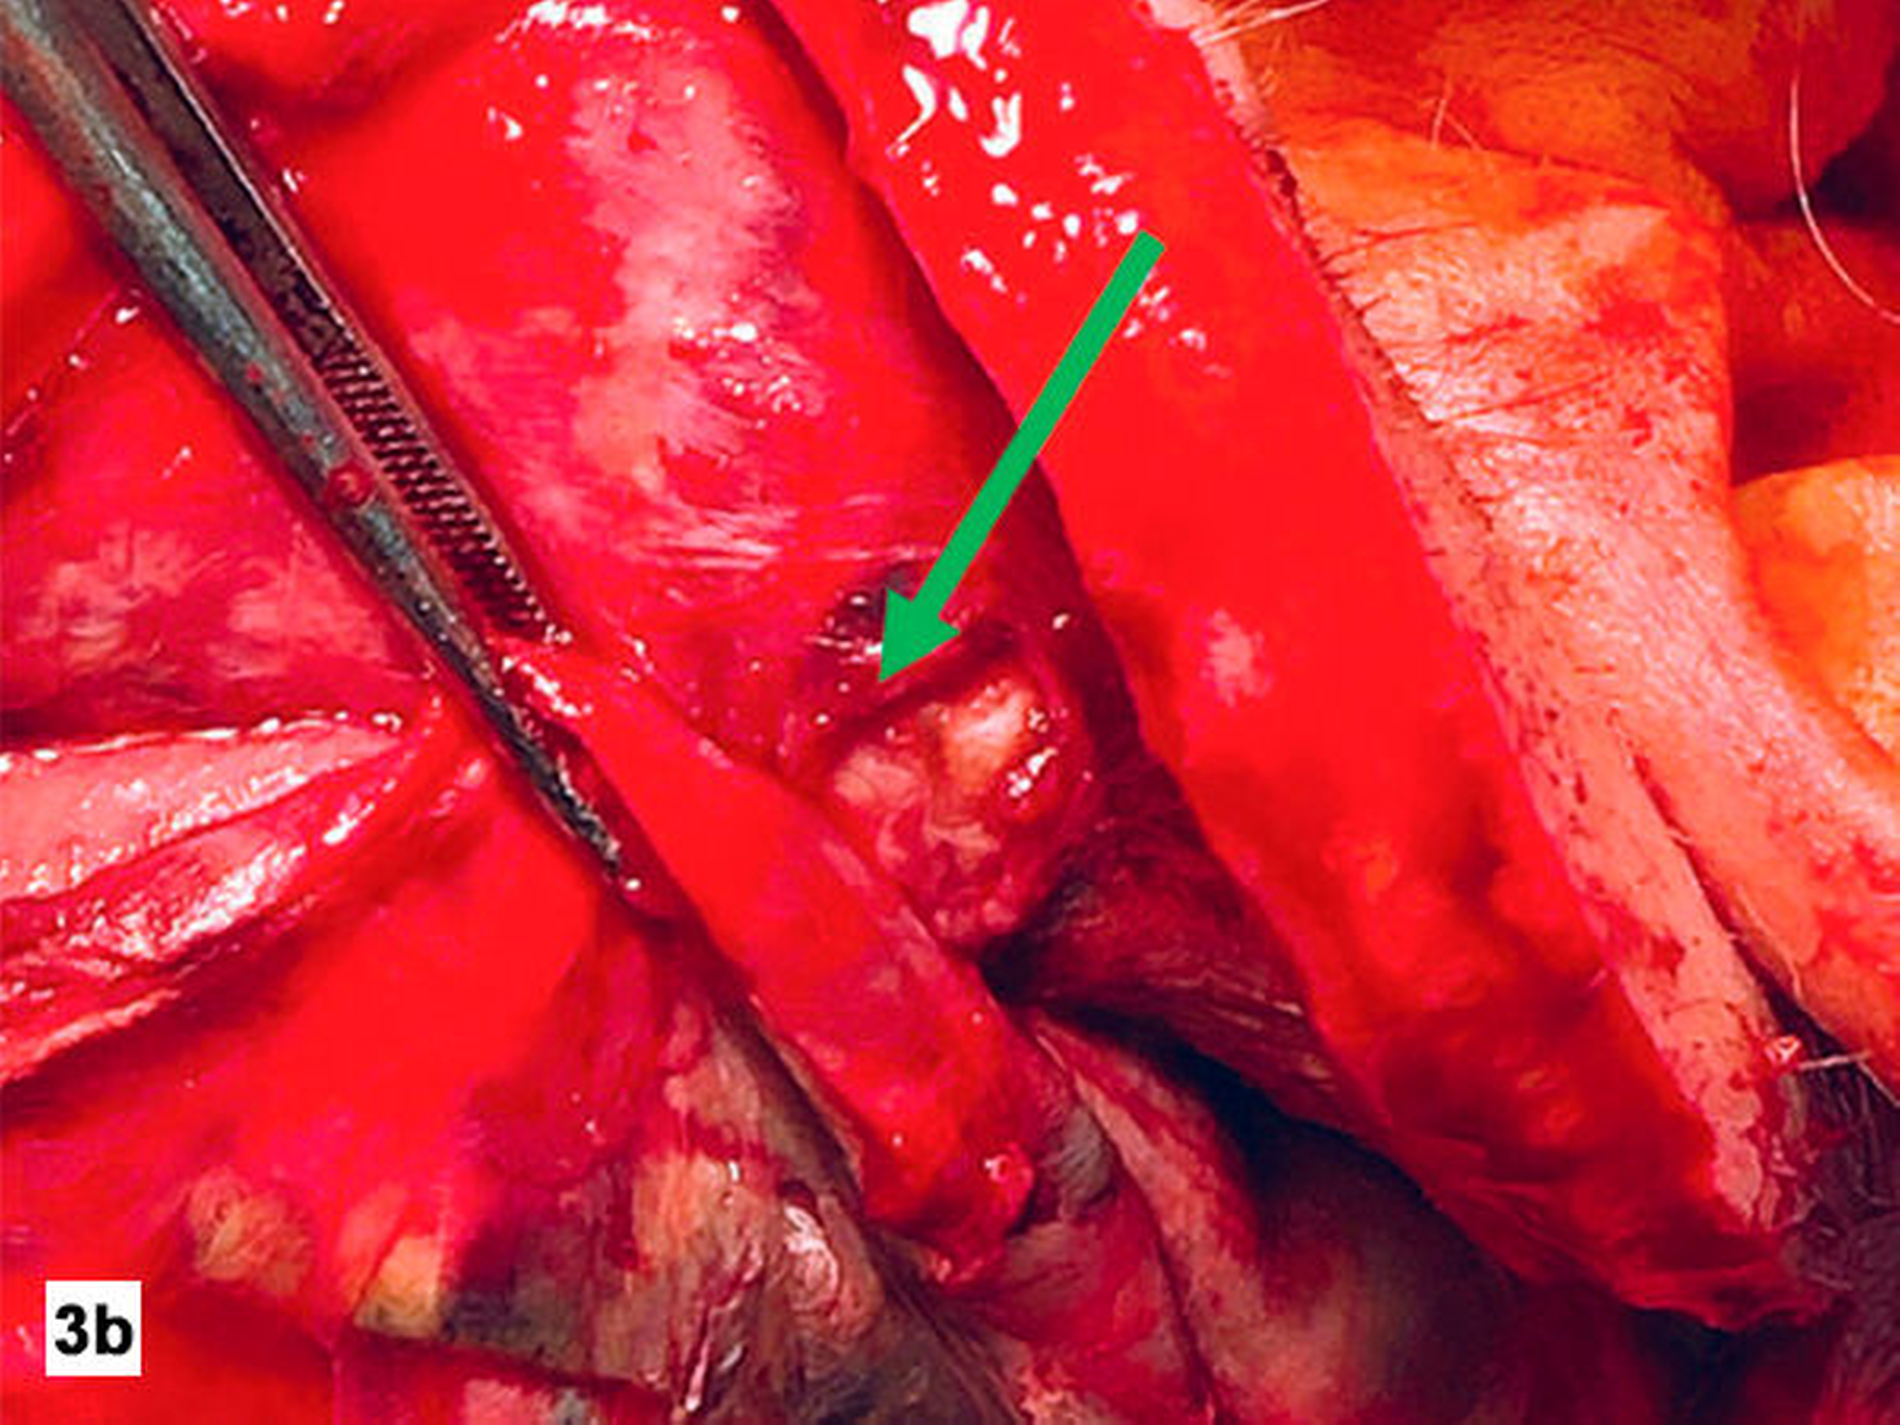

Es erfolgte eine unmittelbare notfallmäßige chirurgische Exploration. Hierbei zeigte sich eine klinisch manifeste Myonekrose der submandibulären, der perimandibulären und der temporalen Kompartimente (Abbildung 3). Die nekrotischen Bereiche wurden entfernt und eine großflächige Lavage mit Polyhexanid-Lösung wurde durchgeführt. Zur Atemwegssicherung wurde der Patient tracheotomiert. Intraoperativ kam es zunehmend zu einer kardiopulmonalen Instabilität, so dass der Patient postoperativ mit septischen Parametern zur weiteren Überwachung auf die Intensivstation verlegt wurde.